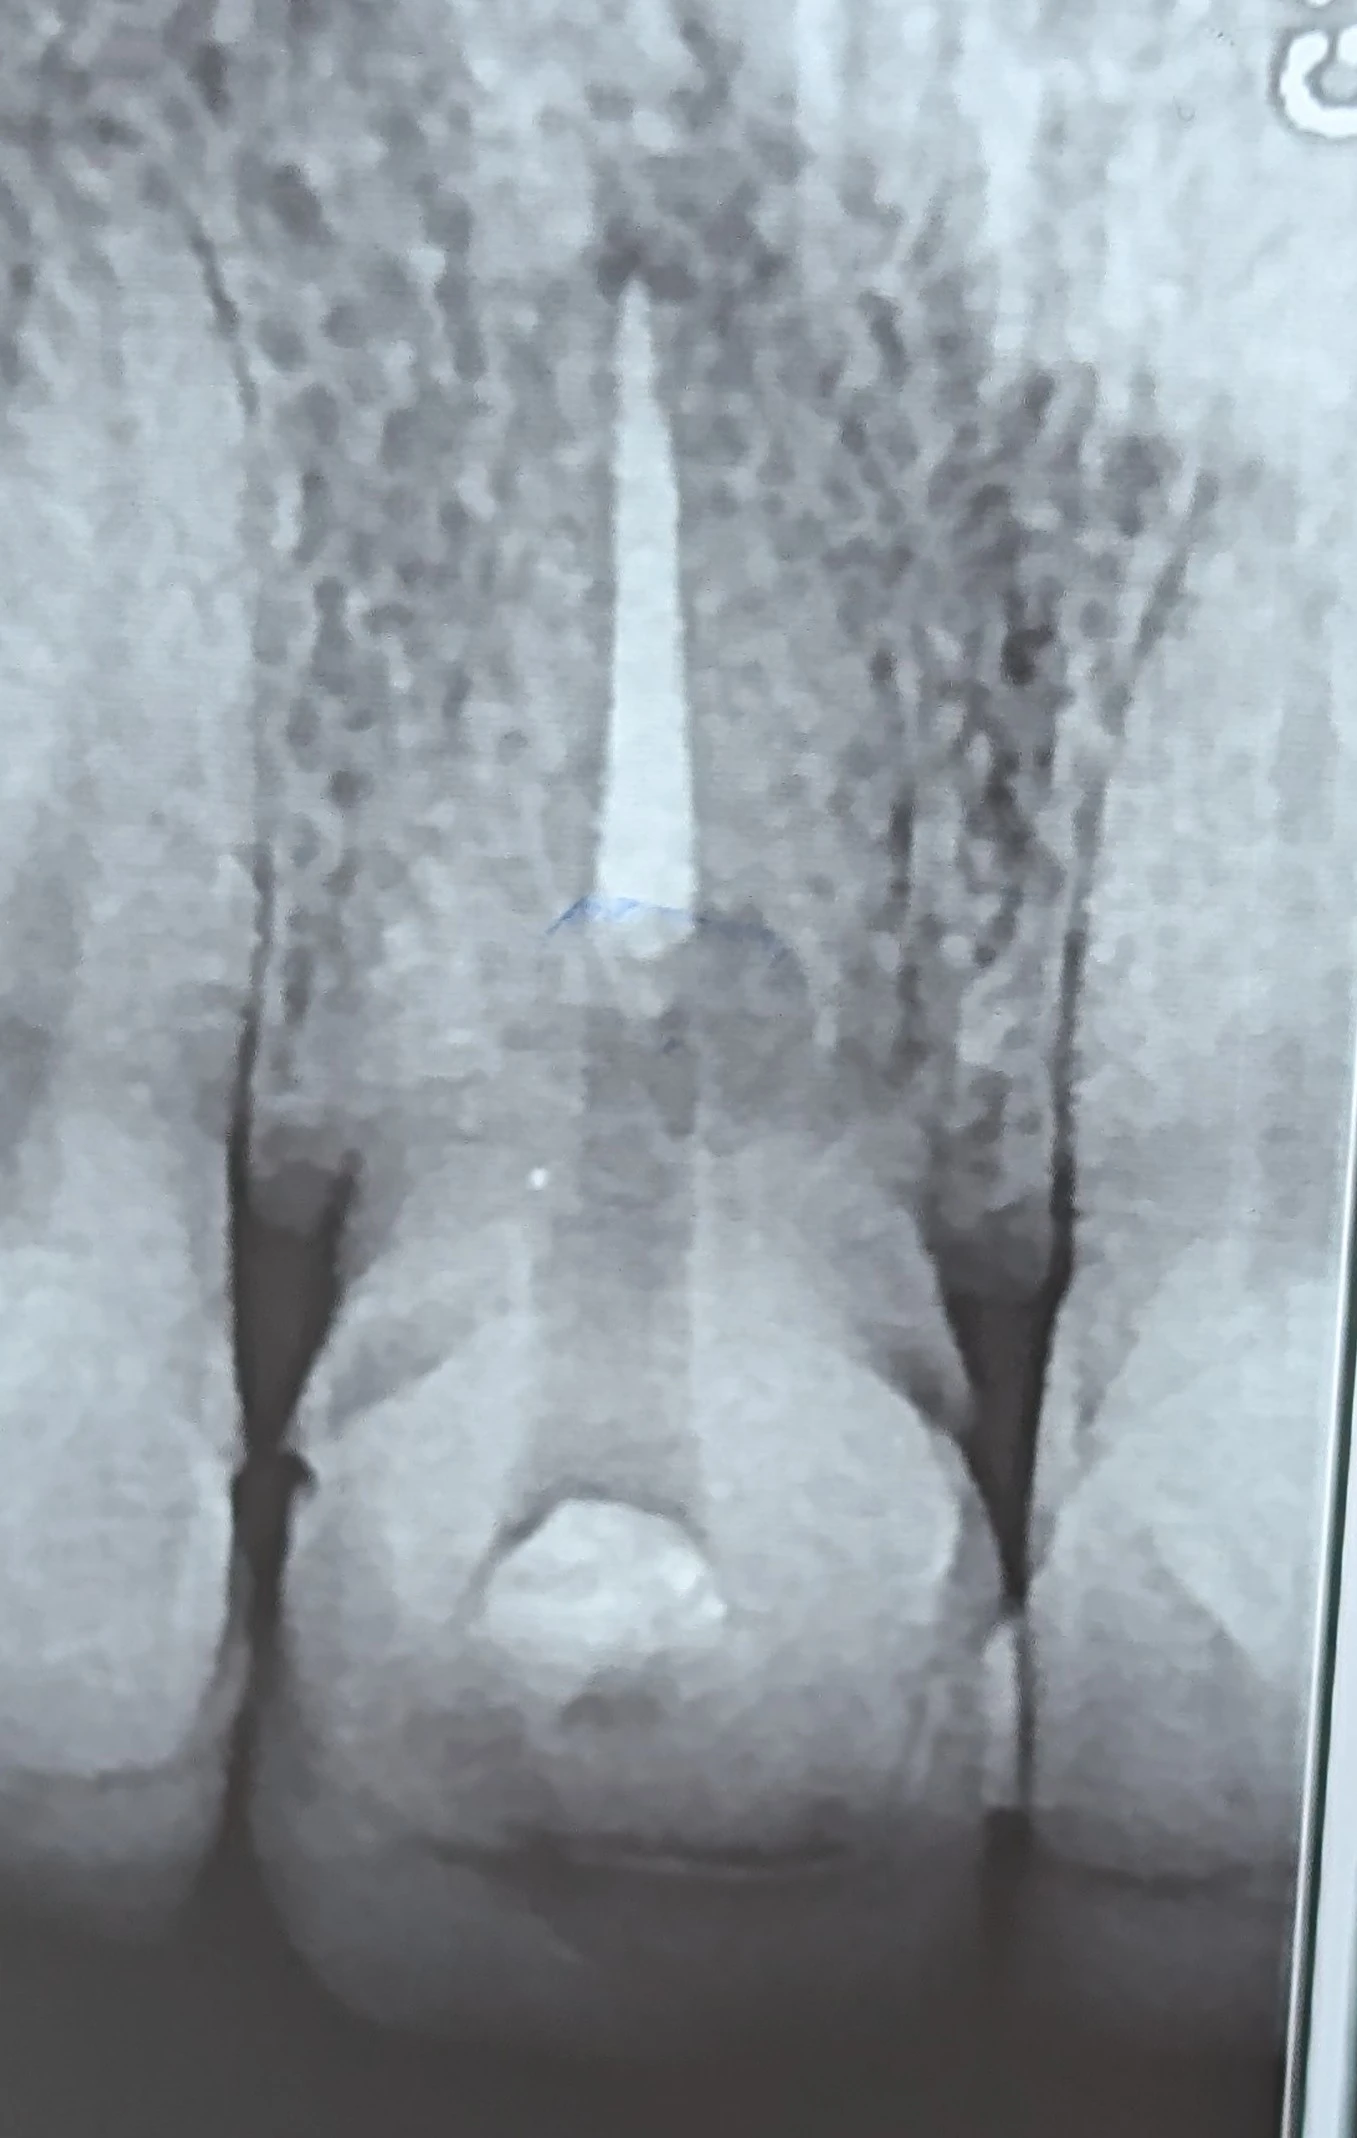

External cervical resorption in anterior tooth

در بررسی رادیوگرافیک، ضایعه‌ای در ناحیه سرویکال دیده می‌شد که با الگوی External Cervical Resorption (ECR) همخوانی داشت. ضایعه به سمت پالپ پیشروی کرده و باعث تضعیف ساختار ریشه شده بود.

در مراحل پیشرفته، این وضعیت اغلب به کشیدن دندان منتهی می‌شود؛ اما اگر حذف کامل بافت رزورپتیو و ایجاد سیل مناسب امکان‌پذیر باشد، حفظ دندان هنوز می‌تواند قابل بررسی باشد.